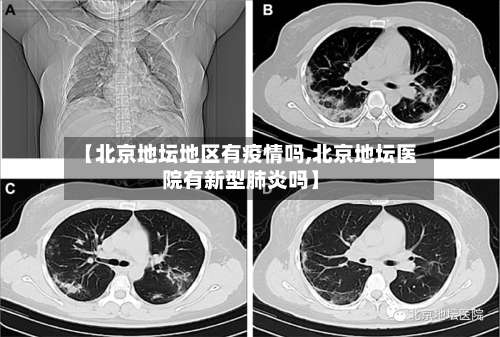

【北京地坛地区有疫情吗,北京地坛医院有新型肺炎吗】